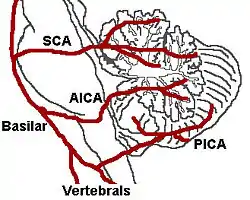

Lateral medullary syndrome is a neurological disorder causing a range of symptoms due to ischemia in the lateral part of the medulla oblongata in the brainstem. The ischemia is a result of a blockage most commonly in the vertebral artery or the posterior inferior cerebellar artery.[1] Lateral medullary syndrome is also called Wallenberg's syndrome, posterior inferior cerebellar artery (PICA) syndrome and vertebral artery syndrome.[2]

It is the clinical manifestation resulting from occlusion of the posterior inferior cerebellar artery (PICA) or one of its branches or of the vertebral artery, in which the lateral part of the medulla oblongata infarcts, resulting in a typical pattern. The most commonly affected artery is PICA, specifically the lateral medullary segment.